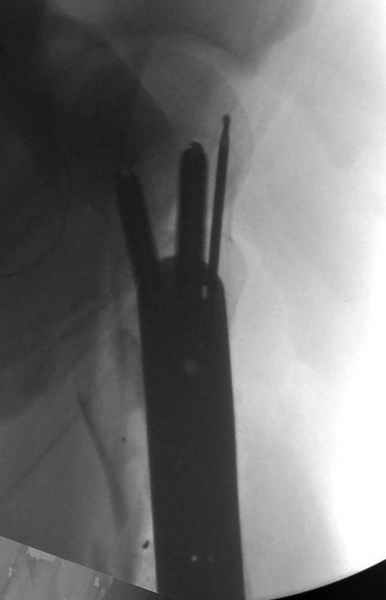

Молодой, с общим состоянием без проблем. Больной соперирован в день поступления и через два дня после операции выписан, так что не успел развиться гной.

Перелом низкоскоростным оружием, типа пистолетного, так что не стали гоняться за пулевыми фрагментами. С нервом пока подождем, иногда нерв восстанавливается если не прямое попадание в нерв, а "сотрясение" (shock wave injury).

Из всех типов фиксации взяли малоинвазивную технику мостовидной пластиной, использовали Locking проксимальную Synthes пластину.